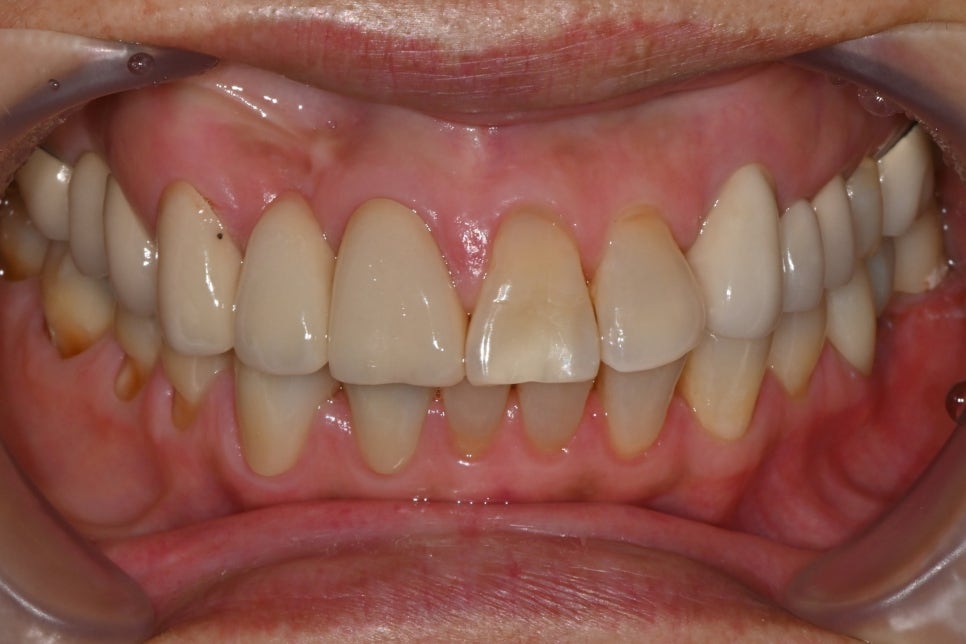

➤초진 진단 소견

앞니 심미 보철과 어금니 임플란트 치료를 계획하기 전, 환자분의 초기 상태를 확인한 모습입니다.

치아 배열, 상실 부위, 기존 보철 상태 등을 종합적으로 진단한 결과, 다음과 같은 치료 계획을 안내드렸습니다:

처음 내원 하셨을때 구강 내 사진

➤ 심미적으로 중요한 앞니 보철이 마무리된 상태로, 자연스러운 치열과 색상 조화를 확인할 수 있습니다.

앞니 #21번 치경부 마모 치료, #43 42 크라운 셋팅 후 정면 사진